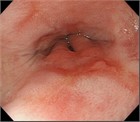

1. 嘔吐、腹痛、腹部膨満、便秘などを主訴に受診した場合には、腸閉塞の診断を行い、その原因として、内ヘルニアを念頭に置いておく必要がある。内ヘルニアによる絞扼性腸閉塞は重篤化するため、早期診断が重要である。早期診断には造影CTが有用であるため、行うことが勧められる(推奨度1 O)

1. 内ヘルニア・横隔膜ヘルニアと診断がつき次第、手術適応である。緊急的に行うか、待機的に行うかについては、造影CTで腸閉塞の状態を把握する必要がある。陥入した腸管を整復し、ヘルニア門を閉鎖もしくは開放する手術を行う(推奨度2 C)

1. 食道裂孔ヘルニアのある場合には胃食道逆流症(GERD)の合併率が高い。胃液の逆流による逆流症状を認め、治療はまず胃酸分泌抑制としてPPIによる治療を行う。内服治療だけでなく、食事指導、生活指導も重要である(推奨度1 M)